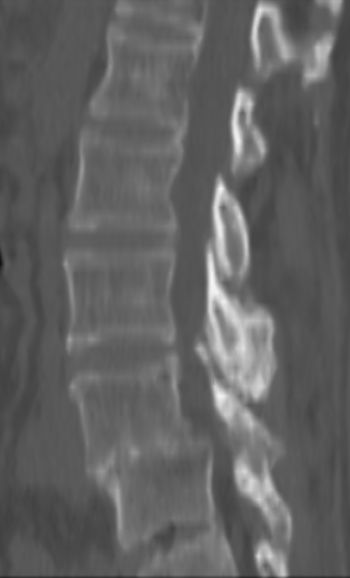

以下是引用余辉在2007-9-4 21:00:00的发言:[br]椎体棘突有点异常(像是被切割了),不知有否手术史,如椎体融合术等。单纯的退行性变可以出现椎间隙变窄,但同时一般会出现椎体上下缘的硬化增生,且椎体间完全融合的机率更小,本例椎体完全融合且椎体上下皮质缘破坏掉了,如果没有手术史,就应该考虑椎间盘炎性病变了,且椎体棘突及棘间韧带的变化也并不是不支持这个,多数小关节也融合了,且其形态也容易让人联想到如强脊炎及类风关等病变。[br][br][本贴已被 余辉 于 2007-9-4 21:03:55 修改过]

以下是引用chry3在2007-9-4 20:42:00的发言:[br]椎间盘病史?是什么样的病史,无双下肢放射痛,那就不是椎间盘突出了。是感染、什么性质的?[br]从图象看椎间隙消失,椎间盘组织未见,锥体滑脱是因为椎间盘溶解造成的[br]l4、5椎体骨质结构未见异常,l5上缘是l4的长期压迫所致[br]还是考虑椎间盘感染,结核。[br]